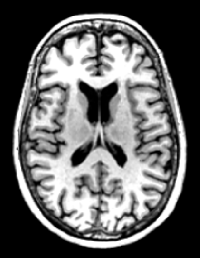

We pre-process the MRI images to use them in the proposed method. There are four steps in the preprocessing phase: (1) anterior commissure-posterior commissure correction using the 3D Slicer software111http://www.slicer.org/; (2) intensity inhomogeneity correction using N4ITK [39], an enhanced version of nonparametric nonuniform normalisation; (3) skull stripping using a pre-trained U-Net222https://github.com/iitzco/deepbrain to remove both the skull and the dura; and (4) rigid registration, which involves linearly aligning MRI images to the Colin27 template and resampling them to a size of 155×185×150155185150155\times 185\times 150 with a resolution of 1×1×1mm3111superscriptmm31\times 1\times 1~{}\mathrm{mm}^{3}. Figure 3 shows a sample of MRI image from ADNI-1 dataset on which the preprocessing is performed.

Figure 3: The visual representation of the preprocessing steps for an MRI sample. (a) A raw MRI image, (b) the MRI image with anterior commissure-posterior commissure correction (c) the MRI image with intensity inhomogeneity correction, and (4) skull stripped MRI image. The yellow line in (a) and (b) depicts the anterior commissure-posterior commissure line.